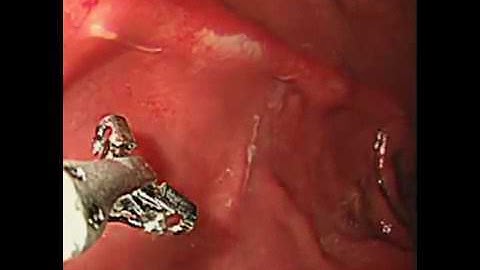

Anisakis simplex